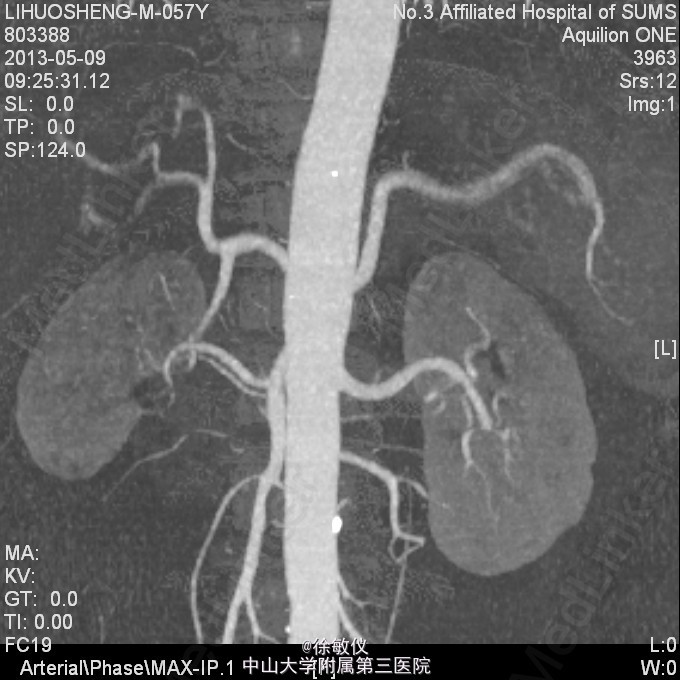

看图片,你的诊断是什么?

老年男性,发现血压升高1年余。平素有降压治疗,但血压控制欠佳,血压最高210/110mmHg,平时血压波动在160-190/90-110mmHg。